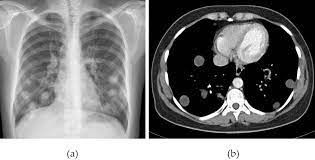

The lungs are the second most commonly affected sites for hydatid cysts after the liver. They may be single or multiple appearing as round-oval lesions. They may erode the bronchus and the resulting air may lead to the appearance of a crescent sign on Xray. They may either be asymptomatic or present with symptoms of dyspnea or cough. Occasionally the patient may cough out whitish material containing the cyst contents if a cyst ruptures into the airways. Cyst rupture is also associated with anaphylaxis. Treatment is largely surgical with the aim of preserving as much viable lung tissue as possible. Image via: https://www.intechopen.com/books/current-topics-in-echinococcosis/radiological-characteristics-of-pulmonary-hydatid-cysts